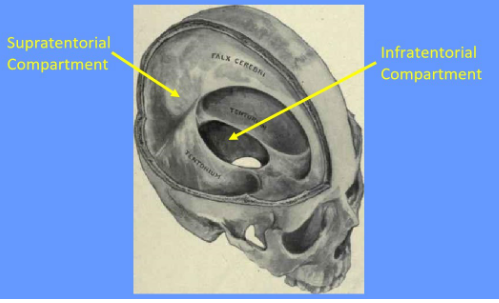

What is the tentorium cerebelli and what does it do

tent shaped fold of dura mater

divides the intracranial cavity into supratentorial and infratentorial compartments

What divides the supratentorial compartment

divided by the falx cerebri into the left and right supratentorial space which can communicate with each other and with the infratentorial space

What is the falx cerebri

vertical fold of the dura mater located in the longitudinal fissure that separates the left and right cerebral hemispheres

Label this image